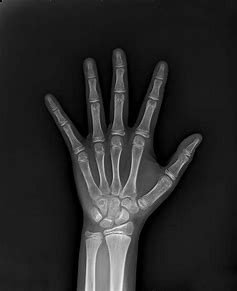

1. 什么是骨龄?

人的生长发育可用两个“年龄”来表示,即生活年龄(日历年龄)和生物年龄(骨龄)。

骨龄即骨骼年龄,在人的生长发育期内,从婴幼儿到成年,骨骼的形态、大小都会有所变化。根据X光片的特定图像确定骨龄,在很大程度上代表了孩子真正发育水平,因此用骨龄来判定人体成熟度比实际年龄更为确切。

通常情况下孩子的骨龄和年龄一般都是相符的,上下浮动不超过1岁,而在疾病状态下骨龄与实际年龄往往不一致。

图片2.png